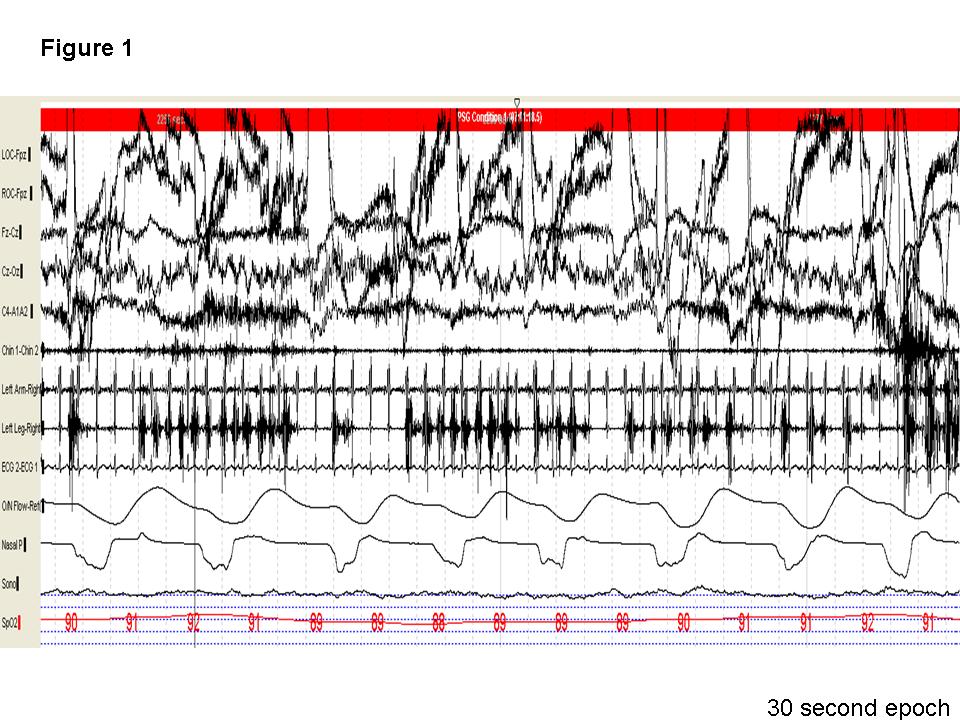

Question: An 83 year-old woman presented to our center for further evaluation and management of snoring, witnessed apneas, restless leg syndrome (RLS), and leg movements during sleep (periodic leg movements). A 30-second epoch (Figure 1) of an incidental finding that was noted during the polysomnogram (PSG) and a video fragment are shown. What is the noted finding?

Discussion: Note the presence of recurrent right leg movements (left leg is covered by a sheet) in the first 10 seconds and the last 15 seconds of the video as the patient transitions from wake to stage N1 and in stage N1 respectively. Similarly, the 30-second epoch shows recurrent electromyographic (EMG) potentials at 1-2 Hz in the right leg with burst potentials greater than 250 milliseconds, lasting for longer than 10 seconds. This meets the criteria for hypnagogic foot tremors(1). Though alternating leg muscle activation (ALMA) is also a possible diagnosis, the surface EMG recorded activity (Figure 2) only from the right (indicated by the red box) and not from the left anterior tibialis muscle (highlighted by blue on figure 2). Of interest, periodic leg movements during wakefulness and not during sleep were also noted in our patient (Figure 3, red arrows).